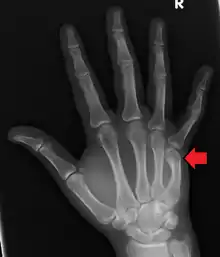

A boxer's fracture is the break of the 5th metacarpal bones of the hand near the knuckle.[4] Occasionally it is used to refer to fractures of the 4th metacarpal as well.[1] Symptoms include pain and a depressed knuckle.[2]

| Boxer's fracture of the 5th metacarpal head from punching a wall | |

Classically, it occurs after a person hits an object with a closed fist.[3] The knuckle is then bent towards the palm of the hand.[3] Diagnosis is generally suspected based on symptoms and confirmed with X-rays.[3]

Diagnosis by a doctor's examination is the most common, often confirmed by x-rays. X-ray is used to display the fracture and the angulations of the fracture. A CT scan may be done in very rare cases to provide a more detailed picture.